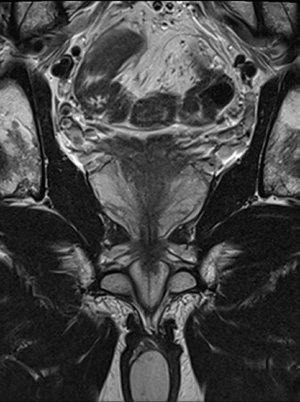

Magnetická rezonance (MR) zobrazuje především klinicky signifikantní nádory prostaty, ložiska musejí být dostatečně velká a musejí obsahovat určitý podíl komponenty Gleasonova skóre (GS) 4 a více, aby byla dobře zobrazitelná. Díky tomu se může značný počet mužů se zvýšenou hodnotou prostatického specifického antigenu (PSA) za určitých podmínek vyhnout biopsii prostaty. Z literatury i ze zkušeností našeho pracoviště vyplývá, že může jít až o nadpoloviční podíl mužů, kteří se díky magnetické rezonanci dozvědí, že s vysokou pravděpodobností nemají nebezpečný karcinom, a biopsie tak není aktuálně potřeba. V rámci následného sledování, které tvoří důležitou součást zmíněných „určitých podmínek“, pak v malém procentu můžeme zachytit i původně MR nezobrazitelný karcinom. Ve studiích všechna tato ložiska zachycená „záchrannou sítí“ byla nanejvýše GS 3+4, tento postup je proto považován za bezpečný. Celý tento proces a jeho benefit pro pacienta ale předpokládají kvalitně provedené MR vyšetření odečtené zkušeným radiologem.

Obecně se senzitivita i specificita MR vyšetření pro detekci karcinomu pohybují v metaanalýzách okolo 80 procent. Pro využití ve screeningu počítáme s využitím tzv. biparametrického MR vyšetření, které neobsahuje postkontrastní sekvence, případně i ve formě zkráceného biparametrického protokolu, který obsahuje pouze transverzální roviny řezu. U těchto redukovaných technik přirozeně klesá diagnostická přesnost, a to zejména u nezkušených radiologů, kde dochází k razantnímu nárůstu počtu nejistých (PI‑RADS 3) lézí, naopak u specializovaných radiologů se zkušeností v hodnocení MR prostaty klesala senzitivita pouze v řádu jednotek procent.

Pětistupňová škála PI‑RADS vyjadřuje pravděpodobnost přítomnosti signifikantního karcinomu, podobně jako systém BI‑RADS u karcinomu prsu. Mezinárodní klasifikace PI‑RADS (aktuálně ve verzi 2.1) je založena na systematickém přístupu k popisu vlastností každého ložiska, umožňuje proto do značné míry objektivizaci výsledku MR vyšetření a slouží jako společný jazyk mezi jednotlivými obory a pracovišti. Stručně řečeno, kdekoliv na světě by měl radiolog popsat ložisko v periferní zóně prostaty s restrikcí difuze a velikostí nad 15 mm jako PI‑RADS 5 a každý urolog z toho pozná, že se s pravděpodobností okolo 80 procent bude jednat o karcinom.

Pro zobrazení karcinomu prostaty je obrazová kvalita naprosto klíčová. Součástí publikace klasifikace PI‑RADS jsou i jasně stanovená kritéria kvality obrazu a jednotlivé parametry MR sekvencí. Například tloušťka vrstvy by měla být vždy 3 mm, pokud přístroj není schopen vytvořit dostatečně kvalitní obraz při této nastavené tloušťce, nemá smysl se o vyšetření prostaty pokoušet. Často diskutována je i síla magnetického pole; je pravda, že kvalitní 3T přístroj bude mít lepší obraz než kvalitní 1,5T magnet, ale z praktického pohledu je důležitější síla gradientů než vlastního pole. Dalším podstatným parametrem je i schopnost radiologického asistenta nebo radiologa z přístroje ten kvalitní obraz získat.